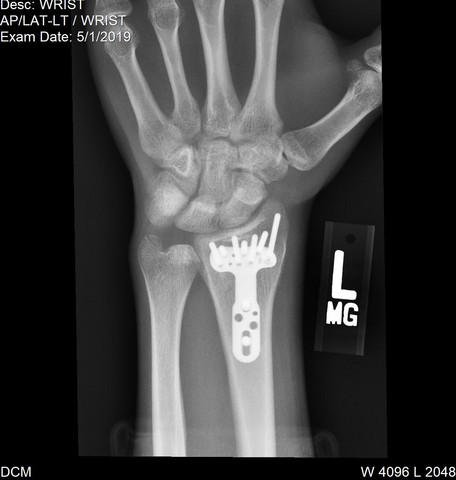

Distale Radius Fraktur Platte Schrauben Rontgenbild Gesundheit Und Medizin Gesundheit Operation